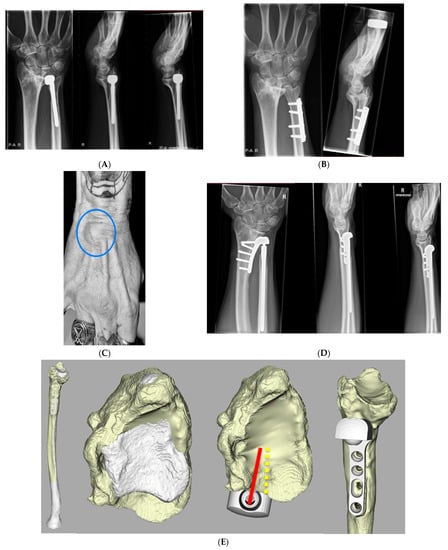

2.5. Radiographic Assessment

3.3. Radiological Evaluation

| Case | Radiological Evaluation | Combined Error | Translation Healthy | Translation Aptis | Δ Translation |

| 1 | Periprosthetic fracture; proximal screws | 11 | 1.5 | 0.5 | −1.0 |

| 2 | Lucency distal screw (37) | 6 | 2.8 | 0.6 | −2.2 |

| 3 | Heterotopic ossification (8) | 7 | 1.3 | 0.2 | −1.1 |

| 4 | No abnormalities | 5 | 2.8 | 0.5 | −2.3 |

| 5 | Heterotopic ossification (4) | 12 | 2.7 | 3.5 | 0.8 |

| 6 | - | 7 | 1.4 | 4.1 | 2.7 |

| 7 | Heterotopic ossification (5) + Lucency distal screw radius (13) | 14 | 2.1 | 0.3 | −1.9 |

| 8 | No abnormalities | 6 | 1.6 | 0.3 | −1.3 |

| 9 | Chip distal ulna (7) + Heterotopic ossification (24) | 13 | 1.8 | 0.3 | −1.5 |

| 10 | Dystrophic calcification (1.5) | 10 | 2.4 | 0.4 | −2.0 |

| 11 | Lucency distal screw (8) + heterotopic ossification (48) | 10 | 1.9 | 2.0 | 0.1 |

| 12 | Heterotopic ossification (57) | 9 | 1.7 | 0.3 | −1.4 |

| Average (SD) | 9 (3) | 2.0 (0.6) | 1.1 (1.3) | −0.9 (1.4) |